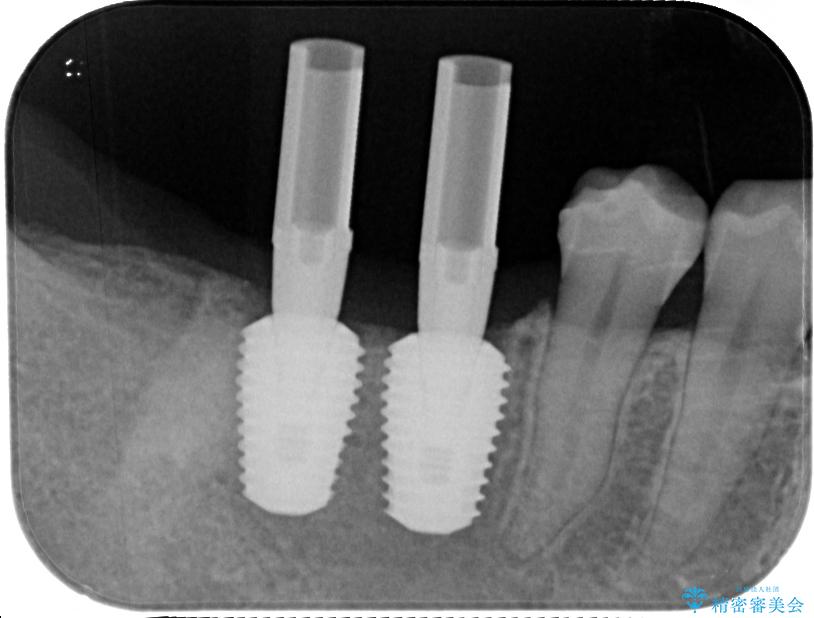

スペースが整った段階で、右下の第一大臼歯と第二大臼歯にインプラントを埋入。

治療途中

• 挺出歯を圧下してスペースを確保!目立たない部分矯正で下顎大臼歯にインプラント治療を実現 治療途中画像